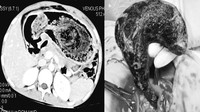

Seorang pria 25 tahun datang menjalani pemeriksaan USG dengan keluhan nyeri perut selama 2-3 bulan. Setelah dilakukan CT scan, dokter menemukan benda logam dalam perutnya. Saat dilakukan laparoskopi, ditemukan banyak isi ulang pulpen dan kawat di dalam lambung pasien. (Foto: F1000 Research)